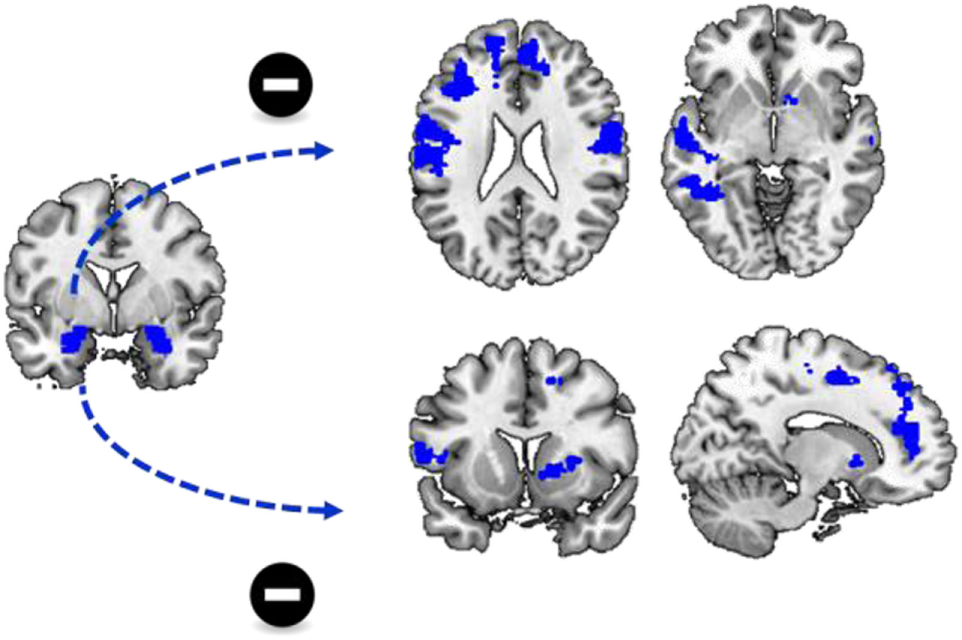

FIGURE 2

www.frontiersin.org

Figure 2. Differences in functional connectivity during cue reactivity. Functional connectivity between the left and right amygdala and a variety of brain regions is significantly reduced during the processing of cocaine cues compared to neutral cues. This includes functional connectivity between the left amygdala and the bilateral insula, inferior frontal cortex and the temporal cortex as well as functional connectivity between the right amygdala and the left insula, inferior frontal cortex and dorsomedial frontal cortex.

Similar to functional connectivity with the left amygdala as seed region, there was no significant group by stimulus type interaction effect on functional connectivity with the right amygdala as seed region. However, there was a significant effect of stimulus type, as there was a stronger functional connectivity of the right amygdala to a variety of regions during the presentation of neutral cues, compared to the presentation of cocaine cues. These regions included the left insula, the left inferior and middle frontal cortex, the right superior and middle frontal cortex, and the bilateral superior medial frontal cortex and the left middle temporal cortex (Table 3; Figure 2).

Differences in Functional Connectivity during Cocaine Cue Reactivity

To assess how cocaine cues altered amygdala connectivity, we performed a PPI analysis. There was no significant group by stimulus type interaction effect on functional connectivity with the left amygdala as seed region. However, there was a significant main effect of stimulus type as there was a stronger functional connectivity of the left amgydala to a variety of other regions during the presentation of neutral cues, compared to the presentation of cocaine cues. These regions included bilateral middle and superior temporal cortex, insula, and inferior frontal cortex (Table 3; Figure 2).